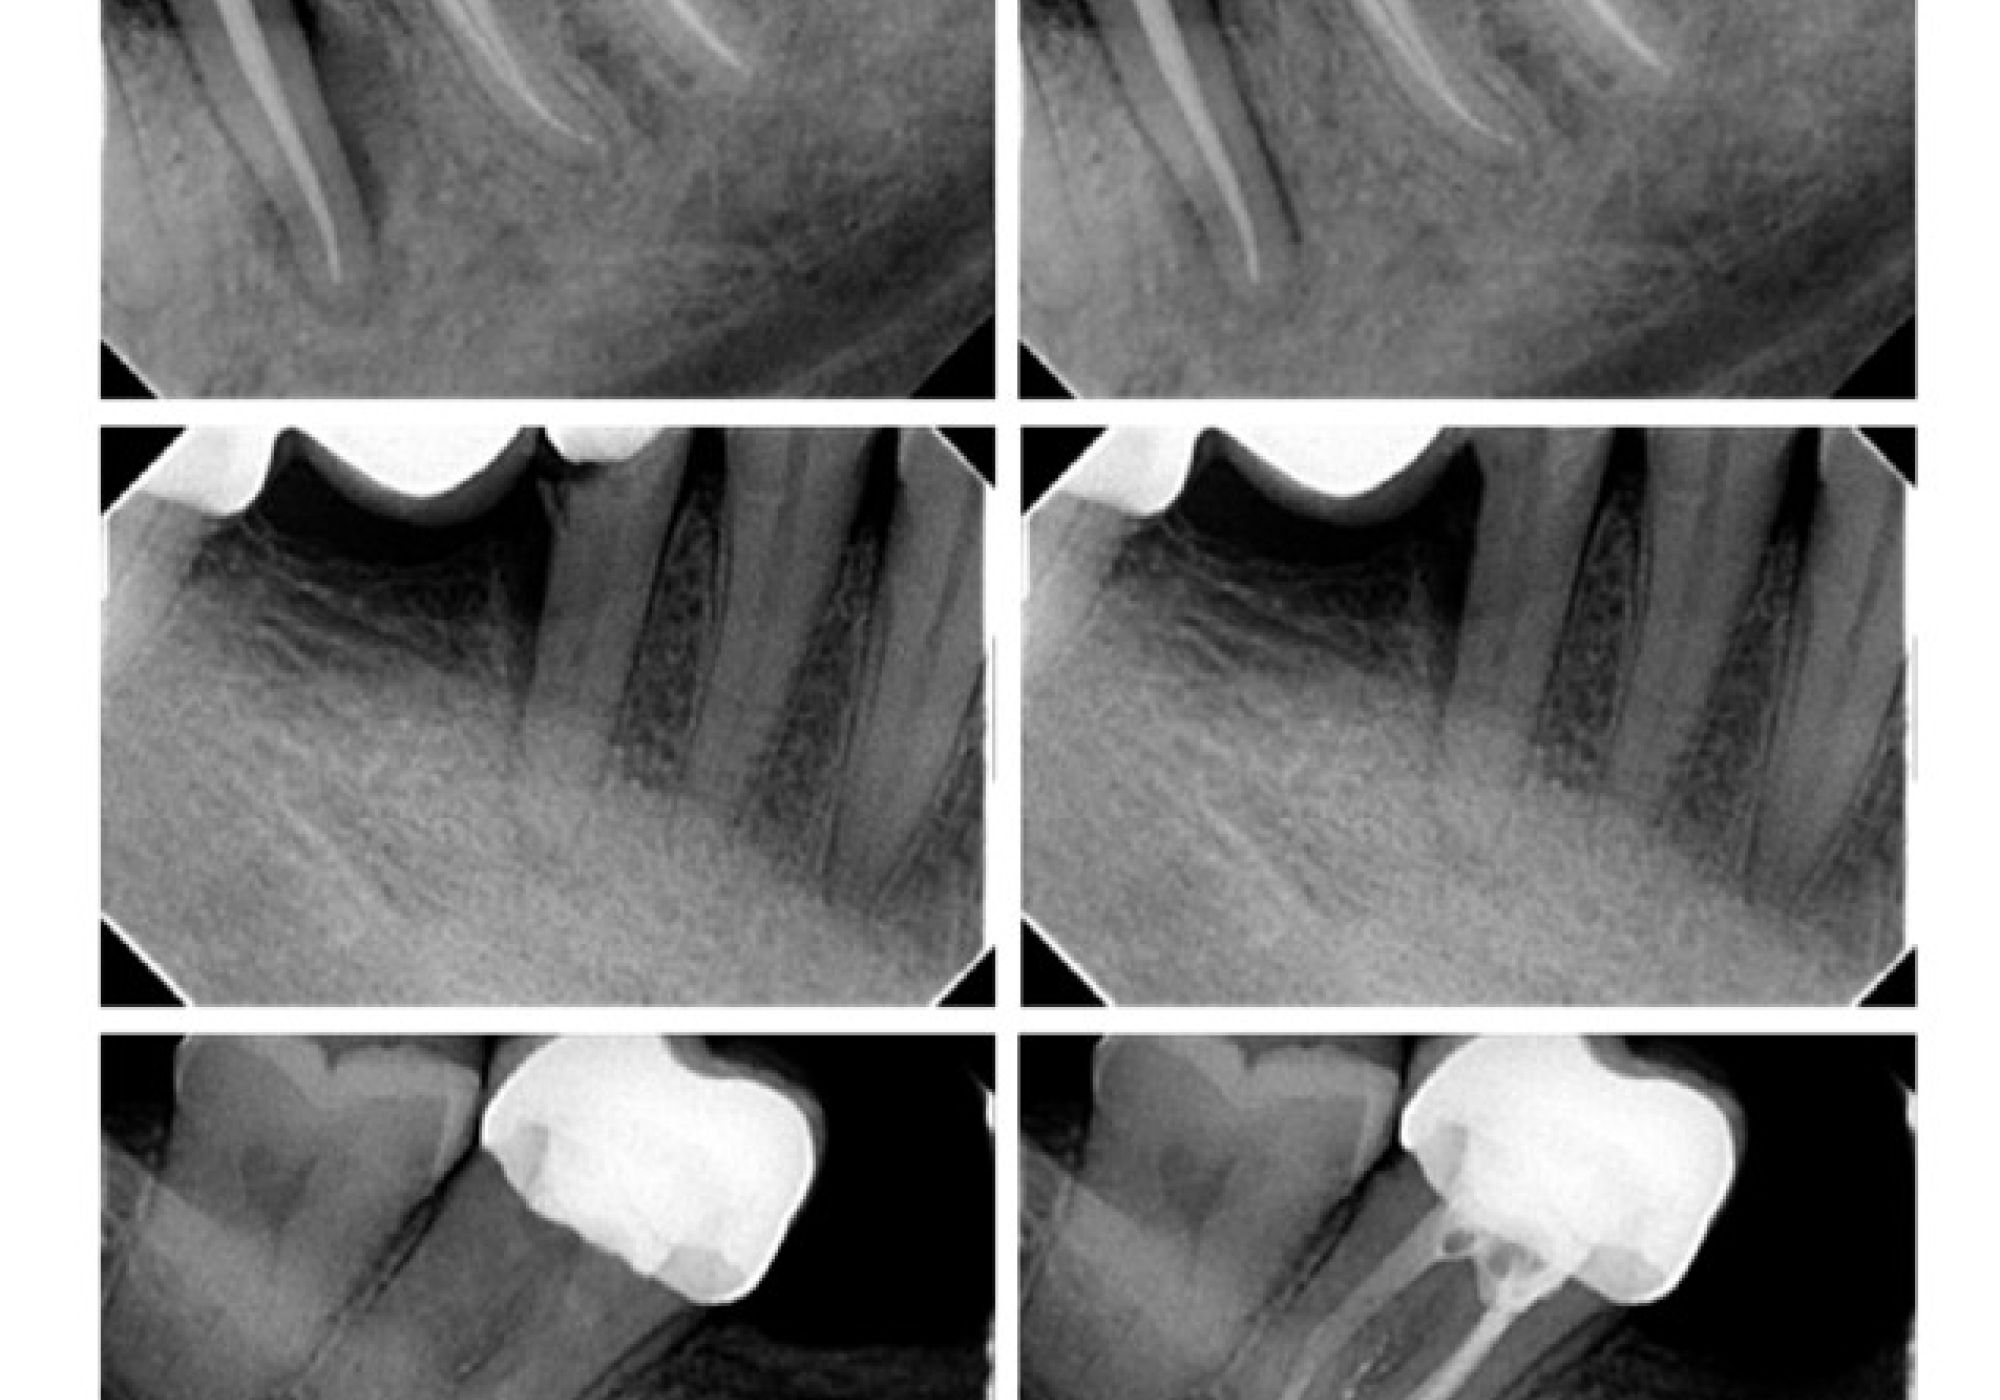

Detección de manipulaciones radiográficas en Endodoncia: la inteligencia artificial en la lucha contra el fraude radiográfico